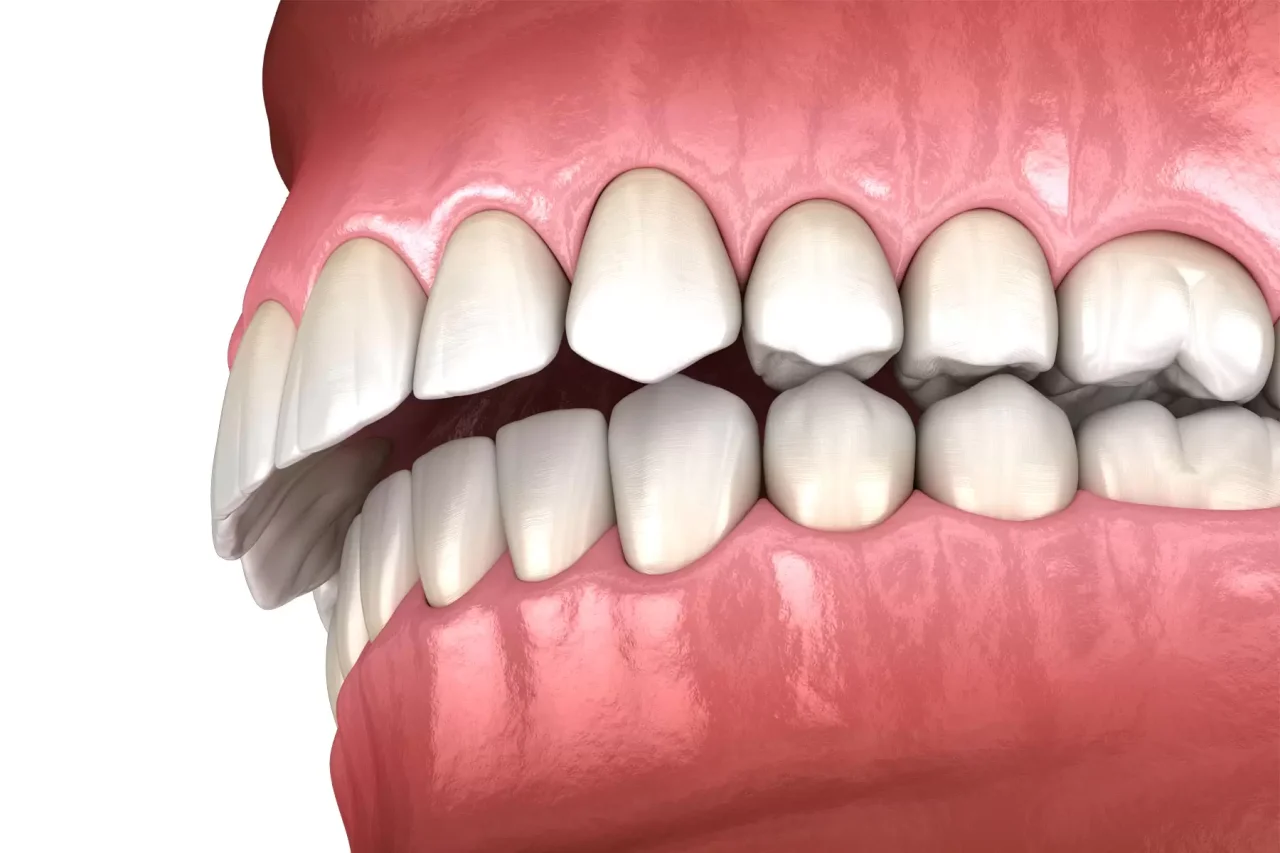

Ajuste Oclusal: Como é feito na ortodontia?

A oclusão dentária exerce influência direta sobre a função mastigatória, a estabilidade do tratamento ortodôntico e a saúde do sistema estomatognático como um todo. Na prática